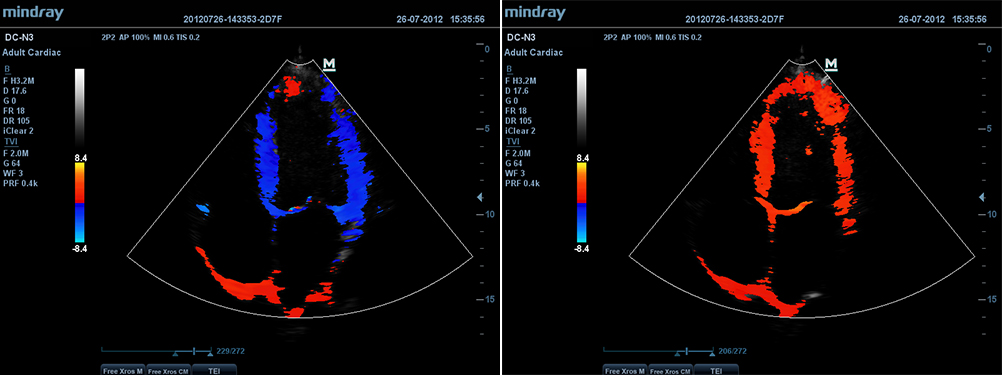

Free Xros CMTM

–Я–Њ–Ј–≤–Њ–ї—П–µ—В –њ–Њ–ї—Г—З–Є—В—М –њ–Њ–ї–љ—Г—О –Є–љ—Д–Њ—А–Љ–∞—Ж–Є—О –Њ –і–≤–Є–ґ–µ–љ–Є–Є —Б–µ—А–і–µ—З–љ–Њ–є –Љ—Л—И—Ж—Л –≤ —А–∞–Ј–ї–Є—З–љ—Л—Е —Д–∞–Ј–∞—Е —Б–Њ–Ї—А–∞—Й–µ–љ–Є—П –Є –Њ–і–љ–Њ–≤—А–µ–Љ–µ–љ–љ–Њ –Њ–њ—А–µ–і–µ–ї—П—В—М —Б—В–µ–њ–µ–љ—М —Б–Є–љ—Е—А–Њ–љ–Є–Ј–∞—Ж–Є–Є –Љ–Є–Њ–Ї–∞—А–і–∞. –Ґ–Њ—З–љ–Њ—Б—В—М —А–µ–Ј—Г–ї—М—В–∞—В–Њ–≤ –Њ–±–µ—Б–њ–µ—З–Є–≤–∞–µ—В—Б—П –≤—Л—Б–Њ–Ї–Њ–є —З–∞—Б—В–Њ—В–Њ–є –Ї–∞–і—А–Њ–≤.

–Т–Є–Ј—Г–∞–ї–Є–Ј–∞—Ж–Є—П –≤ —А–µ–ґ–Є–Љ–µ —В–Ї–∞–љ–µ–≤–Њ–є –і–Њ–њ–њ–ї–µ—А–Њ–≥—А–∞—Д–Є–Є (TDI)

–Ш—Б—Б–ї–µ–і–Њ–≤–∞–љ–Є–µ –≤ —А–µ–ґ–Є–Љ–µ —В–Ї–∞–љ–µ–≤–Њ–є –і–Њ–њ–њ–ї–µ—А–Њ–≥—А–∞—Д–Є–Є –њ–Њ–Ј–≤–Њ–ї—П–µ—В –Њ–њ—А–µ–і–µ–ї—П—В—М –Ї–Њ–ї–Є—З–µ—Б—В–≤–µ–љ–љ—Л–µ –њ–Њ–Ї–∞–Ј–∞—В–µ–ї–Є –і–≤–Є–ґ–µ–љ–Є—П –Є —Д—Г–љ–Ї—Ж–Є–Њ–љ–Є—А–Њ–≤–∞–љ–Є—П —Б–µ—А–і–µ—З–љ–Њ–є –Љ—Л—И—Ж—Л, –њ—А–µ–і–Њ—Б—В–∞–≤–ї—П–µ—В –њ–Њ–ї–љ—Л–є —Б–њ–µ–Ї—В—А —А–µ–ґ–Є–Љ–Њ–≤ —В–Ї–∞–љ–µ–≤–Њ–≥–Њ –і–Њ–њ–њ–ї–µ—А–∞ –і–ї—П —Г–Љ–µ–љ—М—И–µ–љ–Є—П –≤—А–µ–Љ–µ–љ–Є –Є –њ–Њ–≤—Л—И–µ–љ–Є—П —В–Њ—З–љ–Њ—Б—В–Є —Г–ї—М—В—А–∞–Ј–≤—Г–Ї–Њ–≤–Њ–є –і–Є–∞–≥–љ–Њ—Б—В–Є–Ї–Є.